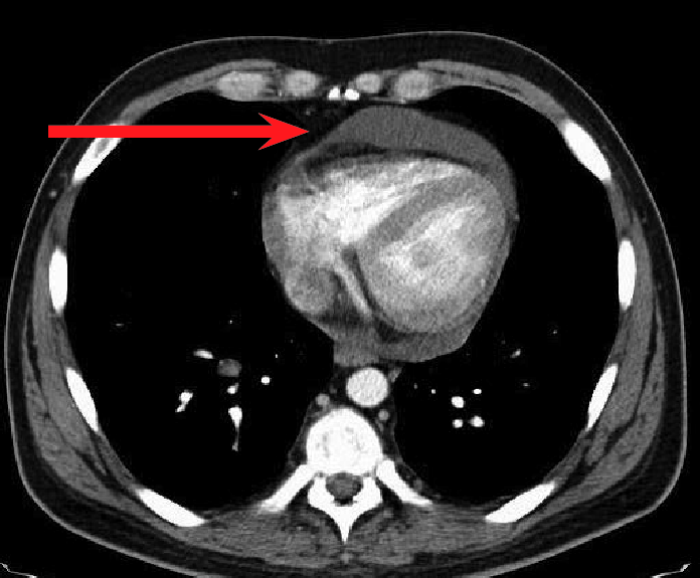

經(jīng)檢查,徐大爺被確診為結(jié)核性心包炎。

“該病起病隱匿,常有心外原發(fā)性結(jié)核病灶或同時有其他漿膜腔結(jié)核性積液存在,易出現(xiàn)長期低熱、盜汗、疲乏無力等癥狀,多無胸痛,易轉(zhuǎn)為慢性,最后形成縮窄性心包炎?!备腥究莆塘亮玲t(yī)生介紹,結(jié)核性心包炎為重癥結(jié)核病之一,對患者生命、生活質(zhì)量均可造成嚴重影響。

確診結(jié)核性心包炎后需要規(guī)律治療,防止病程進展到縮窄階段,降低死亡率。由于徐大爺基礎(chǔ)疾病較多,感染科團隊為其量身定制了個體化抗結(jié)核治療方案。